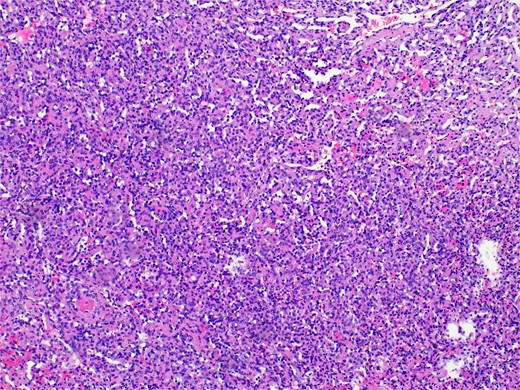

Pathology revealed a benign vascular neoplasm, whose morphological pattern favored AH (Figs 3 and 4).

Histopathology micro findings showing scattered “hobnail” cells.

The name derives from its unique histological characteristics, characterized by blood vessels resembling capillaries organized in a unique anastomosing pattern. The cells lining up the vessels are generally uniform, with minimal atypia and mitotic activity. These cells may also exhibit a “hobnail” morphology, associated with some malignant tumors, including renal cell carcinoma.